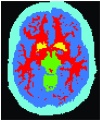

In this section, we review the prior knowledge information devised to improve image segmentation. Table 1 presents some of these important priors and compares them in terms of the nature of achievable solution due to a given formulation (i.e. globally vs. locally optimal), metrication error, domain of action (continuous vs. discrete), and other properties. We also created an interactive online database to categorize existing works based on the type of prior knowledge they use. We made our website interactive so that researchers can contribute to keep the database up to date. Figure 8 illustrates a snapshot of our online database showing different prior information that have been used in the literature for targeted image segmentation.